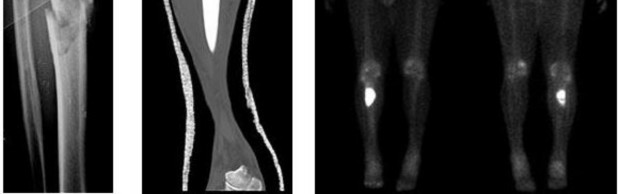

A 15-year-old male presents with deep knee pain awakening him at night. Radiographs show a permeative destructive lesion in the distal femoral metaphysis with a 'sunburst' periosteal reaction and Codman's triangle.

Biopsy confirms high-grade conventional osteosarcoma. What is the most critical prognostic factor for long-term overall survival in this patient?

Explanation

For localized high-grade osteosarcoma, the most important prognostic indicator is the histologic response to neoadjuvant chemotherapy. This is evaluated during the definitive resection. A 'good response' is typically defined as greater than 90% or 99% tumor necrosis. Patients who achieve this level of necrosis have a significantly improved disease-free and overall survival rate compared to 'poor responders' who have extensive viable tumor cells remaining.